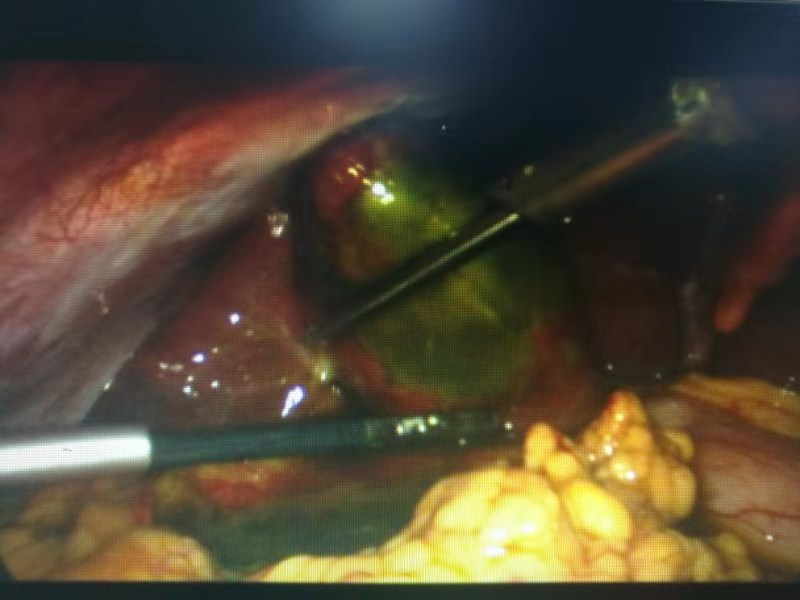

有了周詳?shù)挠?jì)劃,經(jīng)過充分的術(shù)前準(zhǔn)備,手術(shù)開始了。從腹腔鏡下發(fā)現(xiàn),患者膽囊底部壞疽穿孔,膽囊周邊有膽汁滲出。一個(gè)小時(shí)左右,壞疽膽囊和膽結(jié)石被成功取出。

患者術(shù)中照片